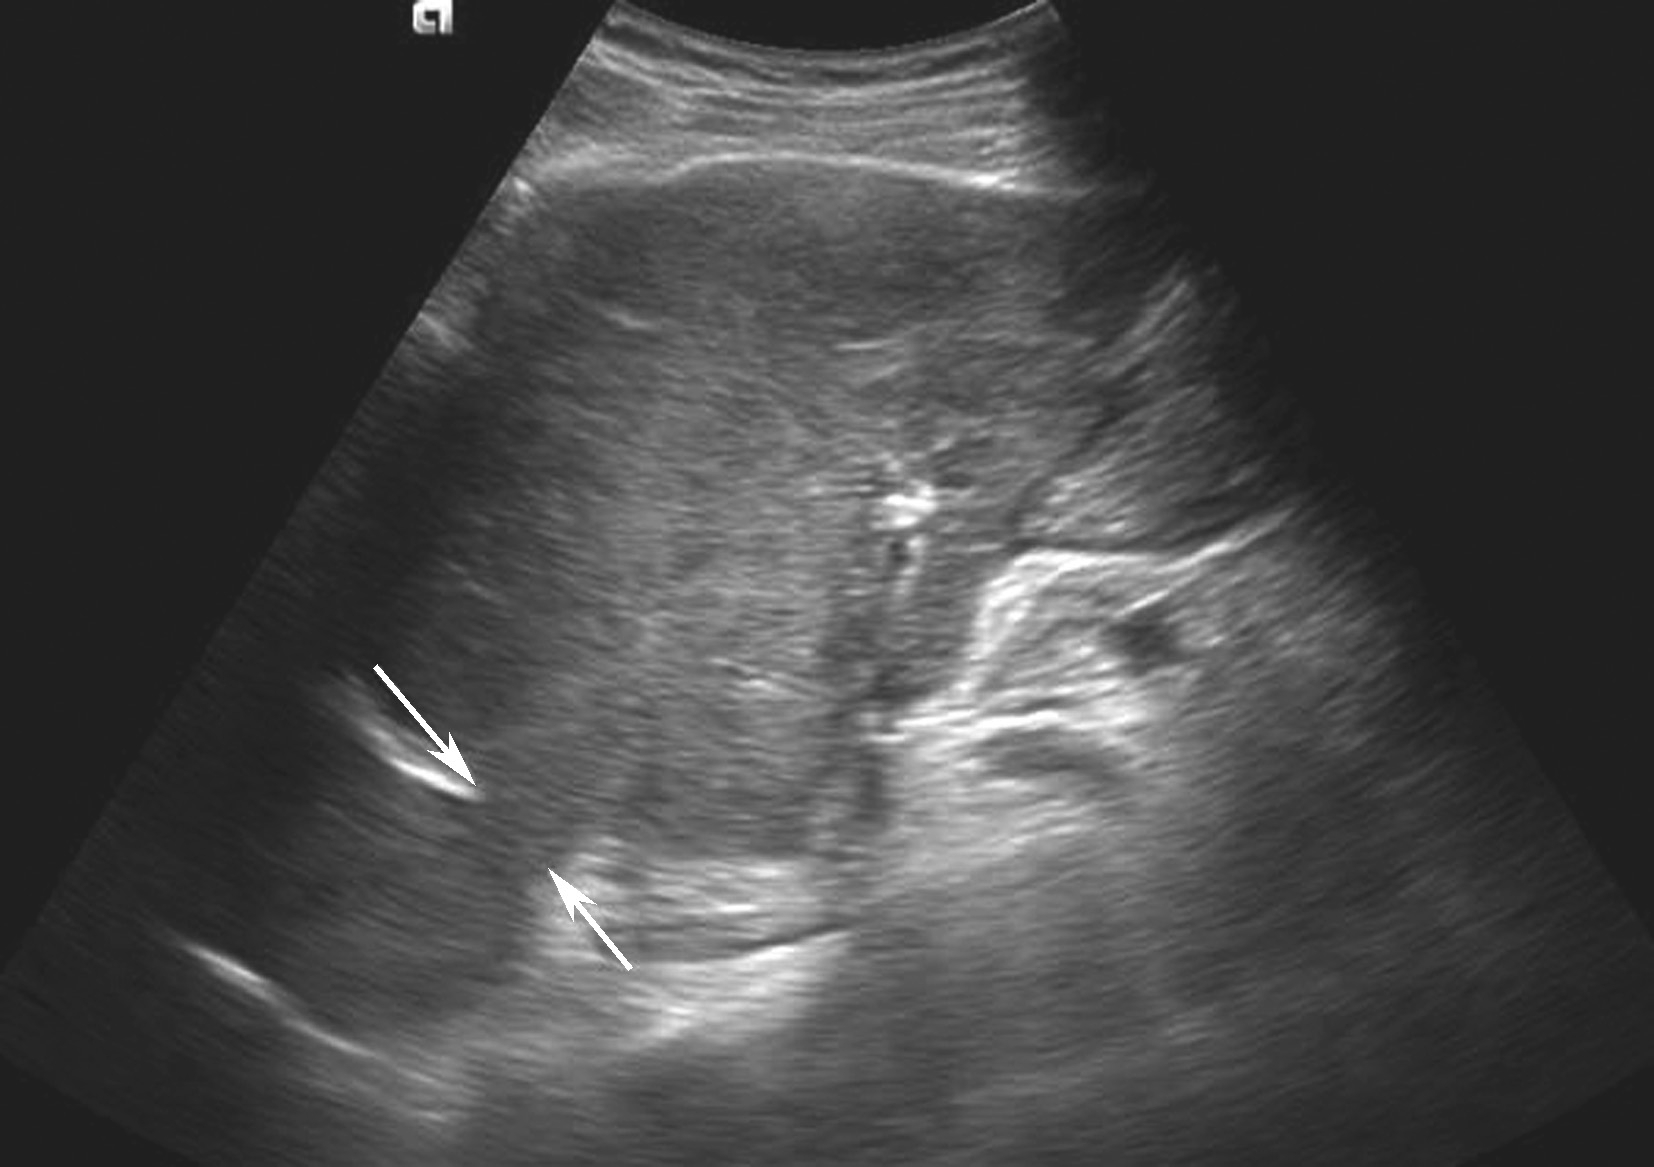

1.灰阶超声

(1)肝脏弥漫性肿大,尤以肝尾状叶增大明显,以肝尾状叶及右肝肿大为主,随病程进展可有肝硬化表现。

(2)下腔静脉近心段(肝后段)狭窄或闭塞,如图5-21-28所示。表现为局部管腔变细、消失,管腔内有膜性、实质性梗阻物或腔外有肿瘤压迫。肝段或肝后段下腔静脉膜性狭窄者管腔内探及线状低回声隔膜斜行,根据隔膜上有无孔分为膜狭窄型和膜闭塞型,远段下腔静脉及肝静脉扩张。

图5-21-28 原发性BCS:下腔静脉膜性梗阻二维灰阶图像